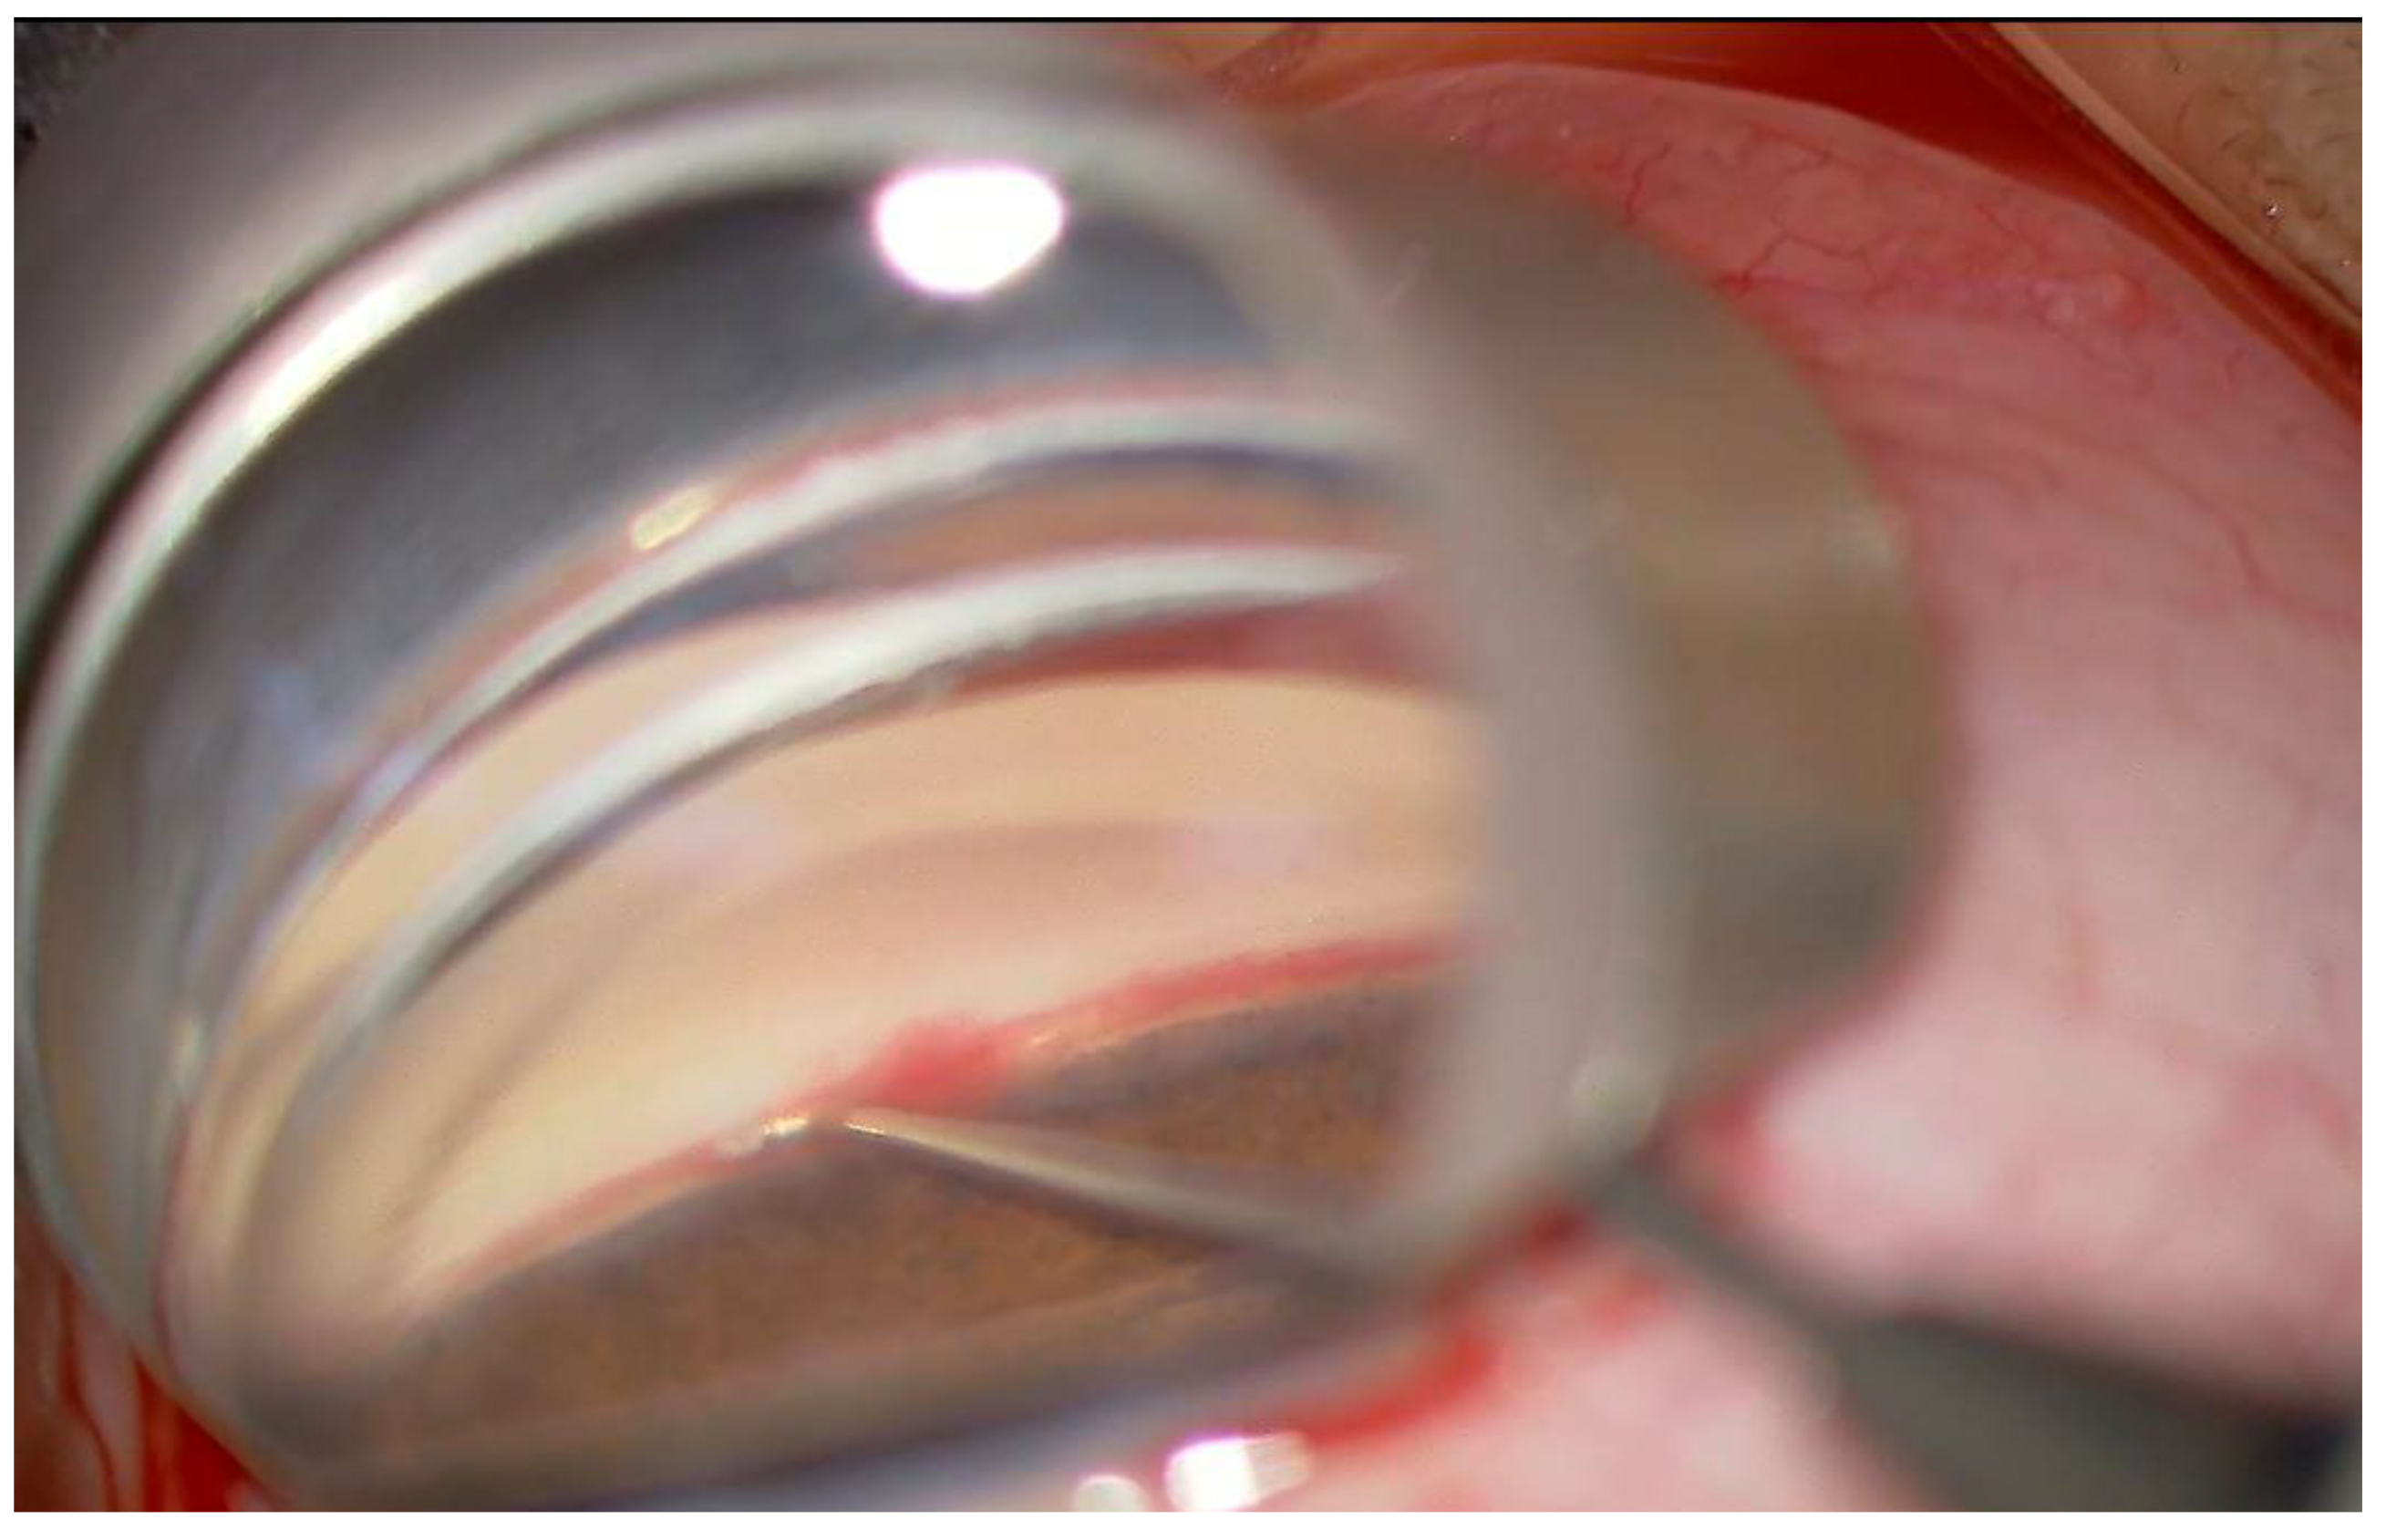

2.2. Surgical Procedure